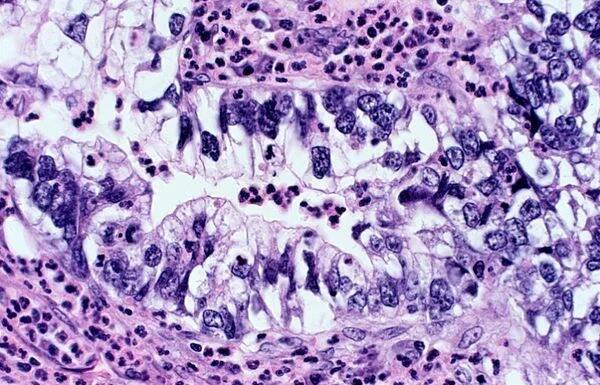

rakovina plic: adenokarcinom - mikroskop - stock snímky, obrázky a fotky

rakovina plic - adenokarcinom, mucinózní typ. pro vybrané případy jsou vhodné terapie specifických genetických mutací (biomarkery egfr, alk, ros1, braf, pdl1, kras). - skvamocelulární karcinom - stock snímky, obrázky a fotky

Fotomikrograf adenokarcinomu plic, ilustrující maligní žlázové buňky charakteristické pro nejběžnější typ karcinomu plic. — Stock obrázek